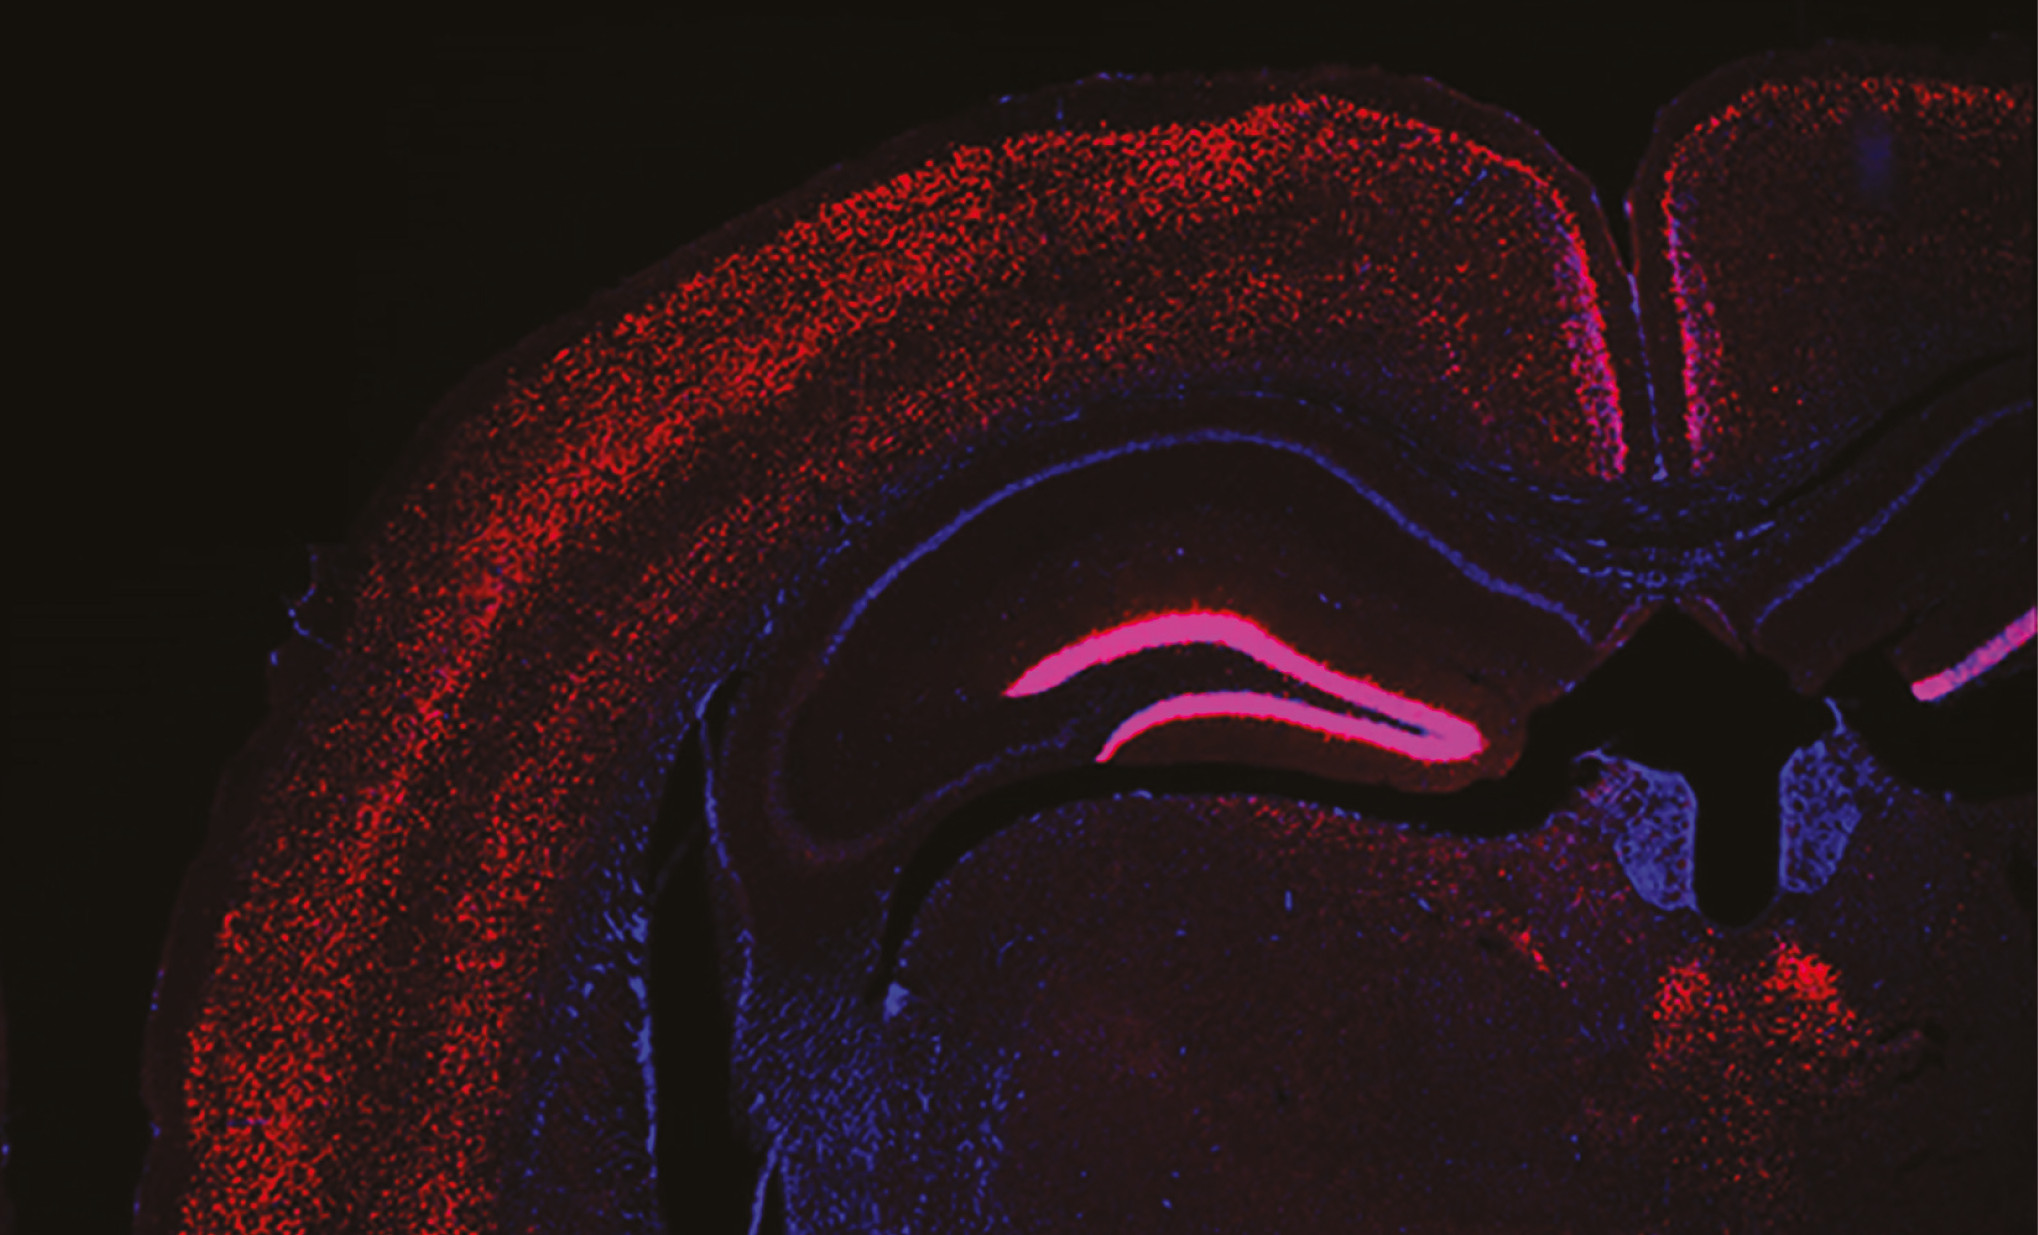

cervell marcat síndrome leigh

Mitjançant tècniques avançades d’imatge, electrofisiològiques i genètiques, l’equip va descobrir que les neurones gabaèrgiques del GPe són particularment vulnerables a la disfunció mitocondrial, fet que condueix a la seva degeneració generalitzada. Com que aquestes neurones són les encarregades de mantenir sota control l’activitat de l’STN, la seva pèrdua fa que aquest nucli es torni hiperactiu, la qual cosa provoca crisis epilèptiques recurrents en els animals.